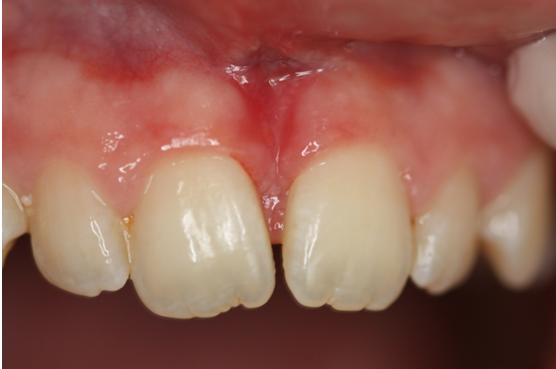

Νεαρός ασθενής που βρισκόταν υπό ορθοδοντική θεραπεία εμφάνιζε έγκλειστο τον κυνόδοντα άνω αριστερά.

Με τη χρήση του Nd-Yag laser έγινε αποκάλυψη του κυνόδοντα, ώστε να γίνει δυνατή η ορθοδοντική μετακίνηση (μετοποθέτηση αγκυλίου-Bracket)

Αρχική κλινική εικόνα

Μετά την αποκάλυψη